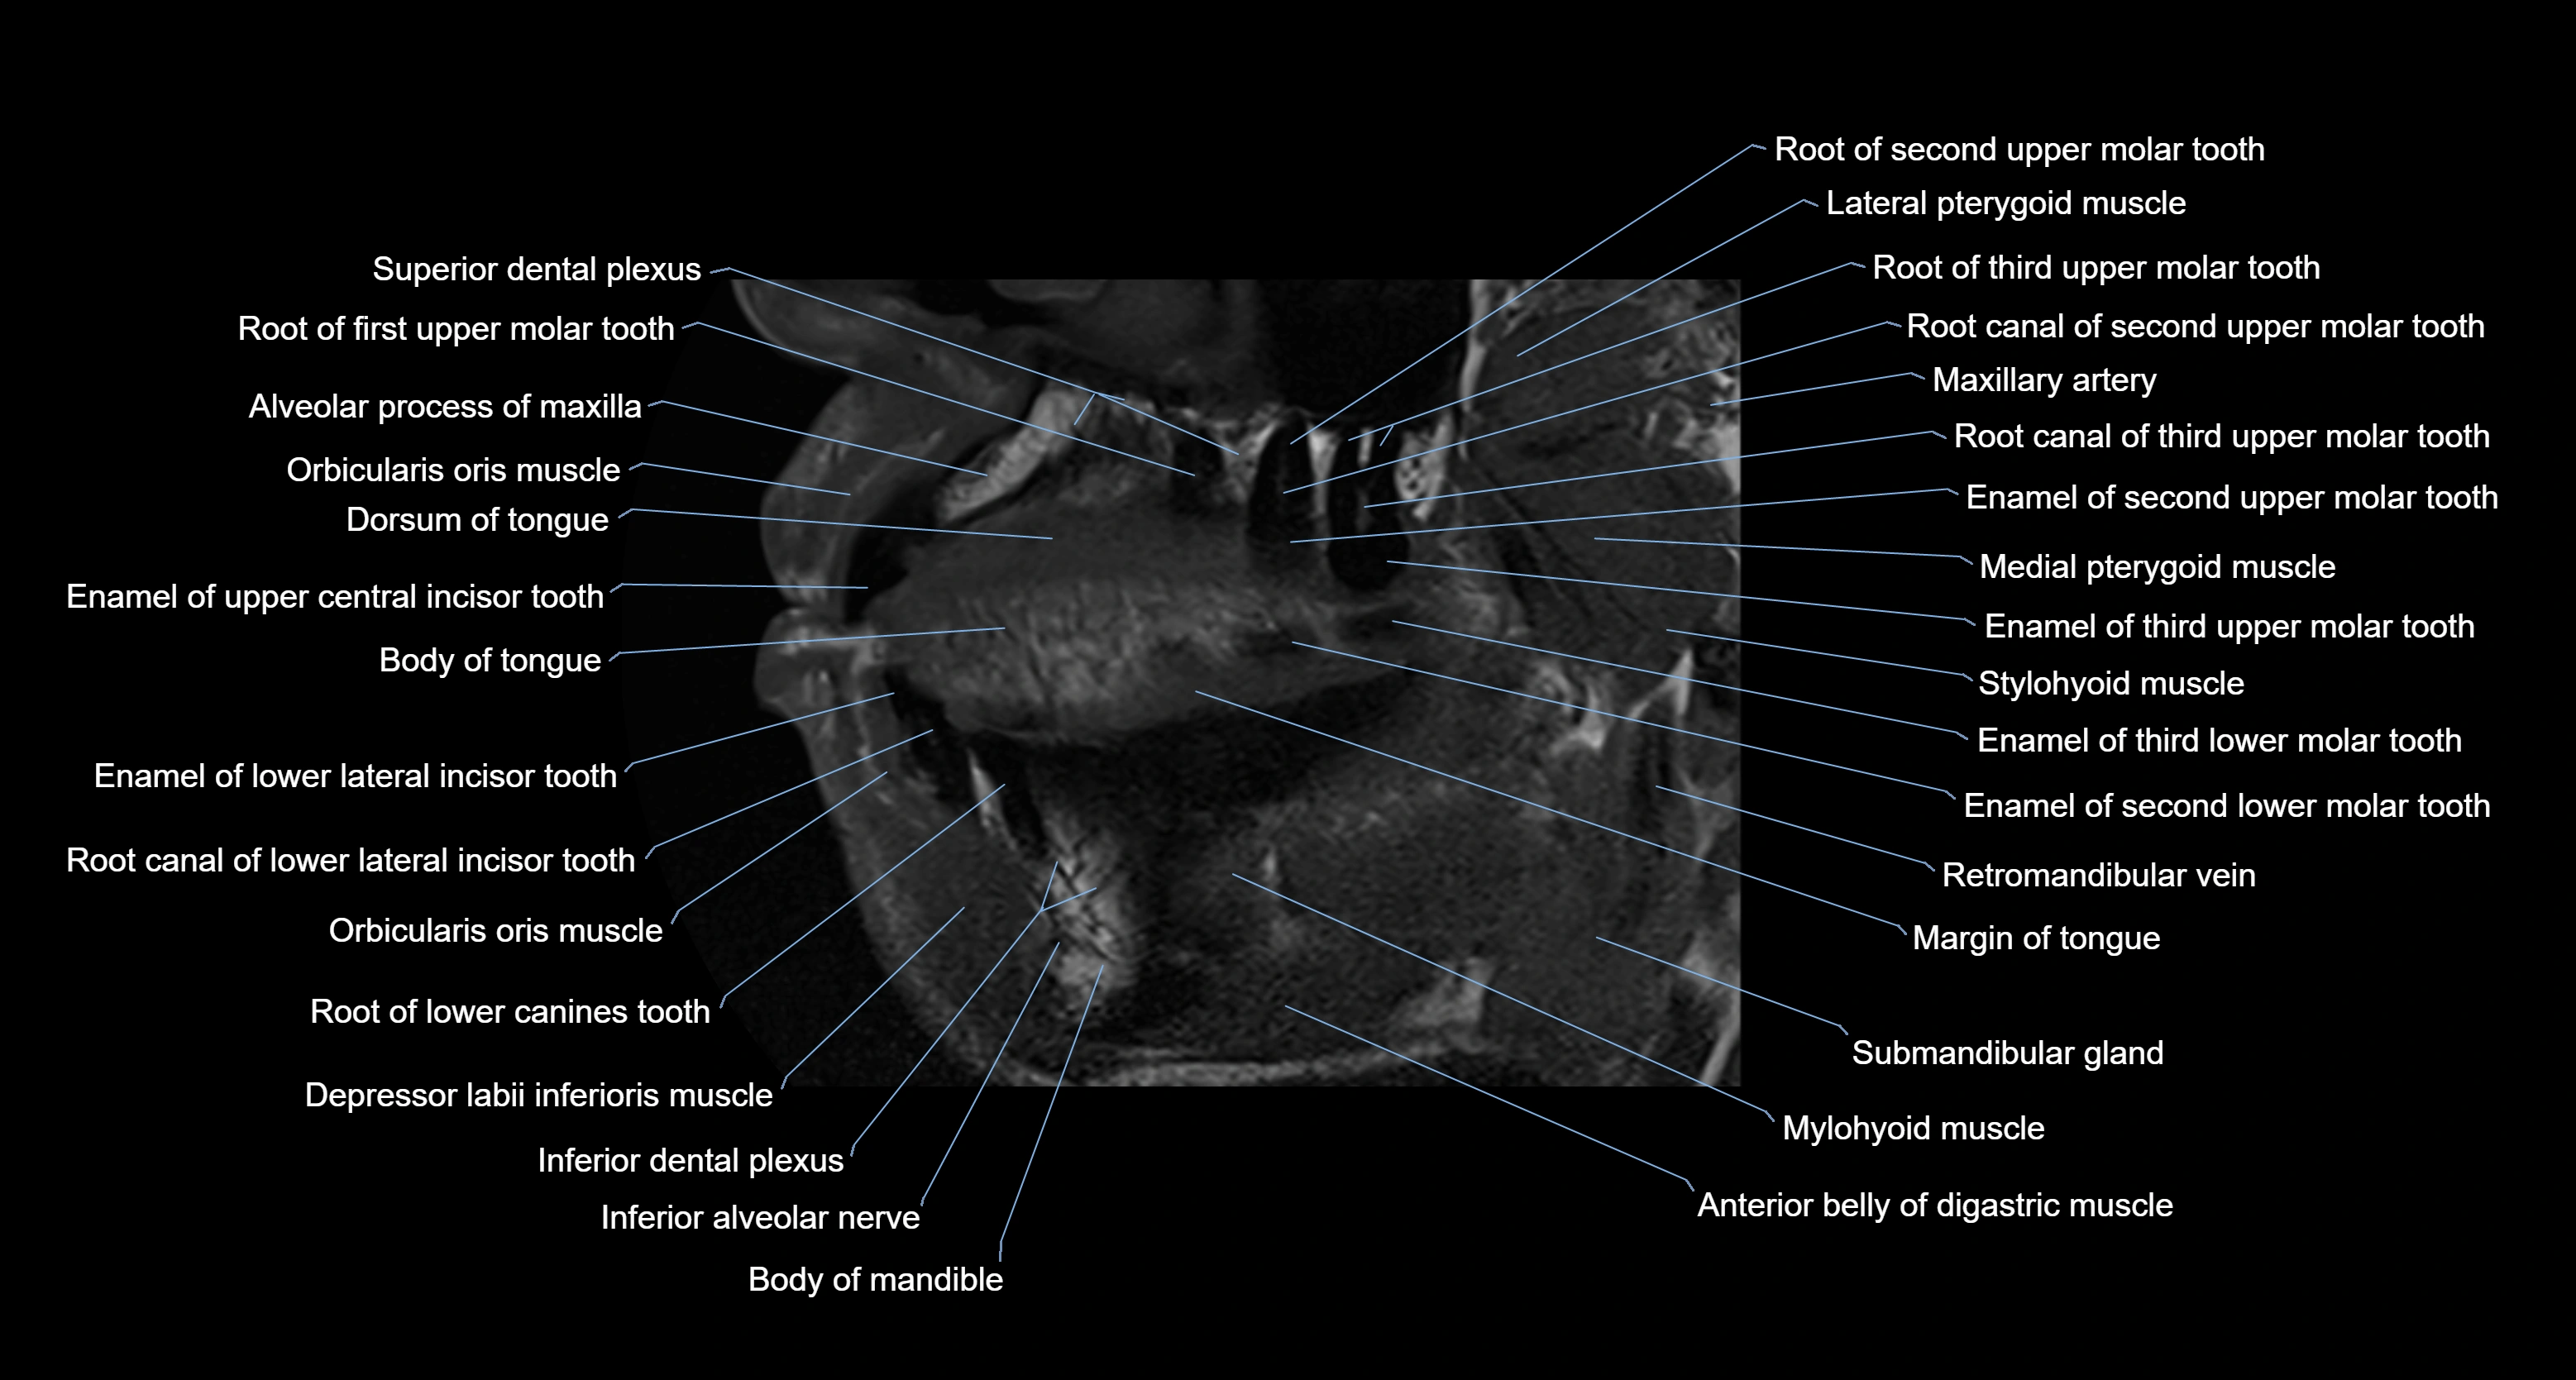

- Anterior belly of digastric muscle

- Body of mandible

- Dorsum of tongue

- Inferior alveolar nerve

- Mylohyoid muscle

- Orbicularis oris muscle

- Posterior superior alveolar nerve

- Ramus of mandible

- Stylohyoid muscle

- Superior dental plexus